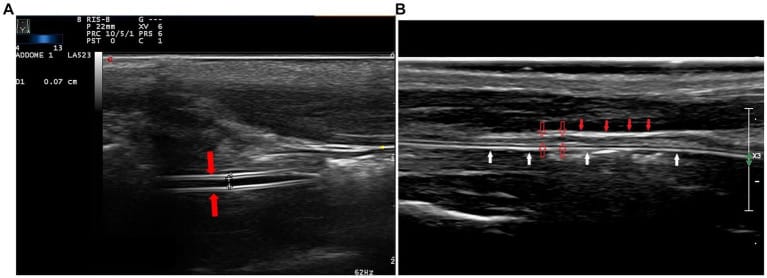

In the longitudinal cervical scan, with a high-frequency linear transducer, the feeding tube was visible as double parallel hyperechogenic lines (A, red arrows). The hyperechoic adventitia (B, full red arrows) and the hypoechoic muscularis (B, empty red arrows) are the most evident layers of the walls of the esophagus; the tube is within the lumen (B, white arrows).